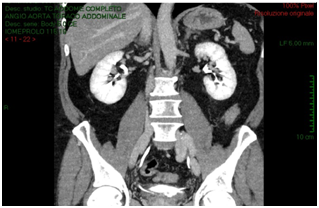

A 54-years old Caucasian man affected by sub renal aortic aneurysm, undertake vascular surgery of aortotomy and bilateral aortoiliac Dacron prosthesis implantation. Patient had a good health status; he had hypertension (with good control of blood pressure), diabetes mellitus type 2. He had no operations. In the past. In 5 post-operative days, due to post-operative anaemia, fever and slight increased creatinine (around 1.3 mg/dl), the patient received an ultrasound scan that showed intra-retroperitoneal fluid without any sign of hydronephrosis. In the suspect of haemorrhage, vascular surgeons performed an abdomen CT-scan with contrast that reported organized hematoma along the right iliac branch associated to intraperitoneal serous-hematic fluid (Figure 1). CT-scan did not have delayed phases. In XII post-operative day, patient was transferred to intensive care ward because of fever until 39°C, dynamic ileus and uremic status. He received an abdomen contrast CT-scan that showed increasing of intra-retroperitoneal fluid with small bowel and right colon compression and increase of right iliac region serous-hematic fluid (Figure 2).

Figure 1: Abdomen CT-scan with contrast that reported organized hematoma along the right iliac branch associated to intraperitoneal serous-hematic fluid.